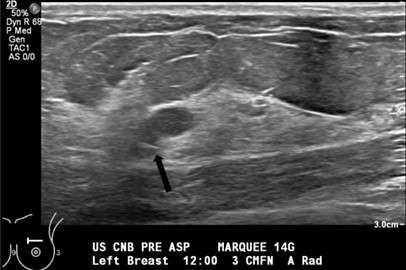

• Technologist saves an image documenting placement of the needle tip (Figure 2).

Procedure: US Guided Cyst Aspiration Figure 2

Figure 2. Grayscale sonogram shows the aspiration needle tip (black arrow) within the more posterior cystic structure.